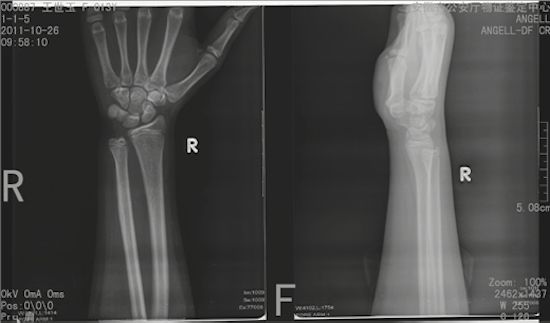

可是,如何观察被鉴定人的骨骺愈合程度呢?因为观测点主要是四肢长骨的两端,所以法医“蜀黍”们的办法是带

被鉴定人去拍摄全身六大关节的X片(关节就是长骨一端对接的地方)。所谓的六大关节就是肩关节(观察肱骨上端和肩胛骨)、肘关节(观察肱骨下端以及尺骨、桡骨上端)、腕关节(观察尺骨、桡骨下端以及诸手骨、掌骨和指骨)、髋关节(观察骨盆以及股骨上端)、膝关节(观察股骨下端和胫骨、腓骨上端)和踝关节(观察胫骨、腓骨下端以及诸足部骨骼)。

不足18岁的可以看到骨骺线